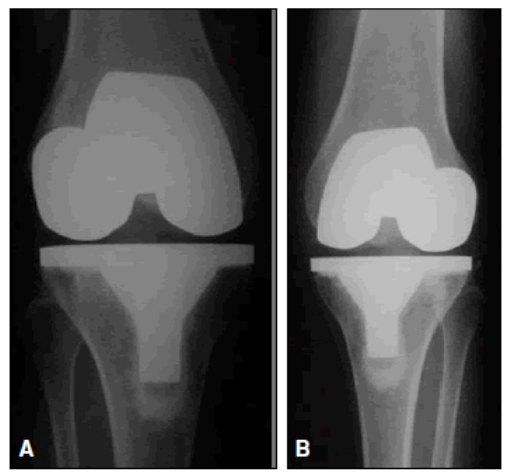

- CIRUGÍA DE LA ARTROSIS: